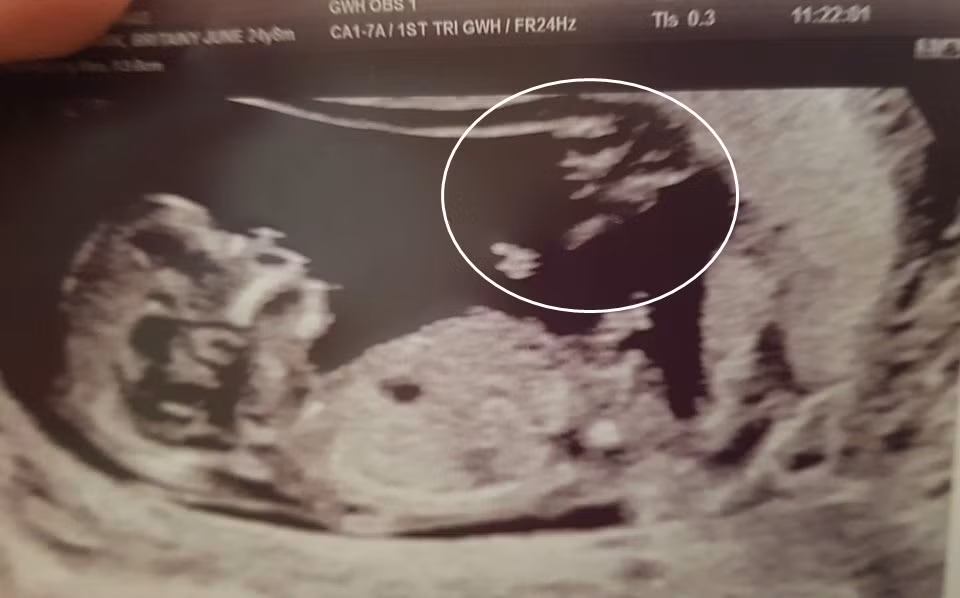

Đến bệnh viện kiểm tra, Britainy vô cùng ngạc nhiên và hạnh phúc khi biết tin mình đã mang thai được 12 tuần. Ngay sau đó, Britainy đã được các bác sĩ siêu âm thai.

Bức ảnh siêu âm vẫn khiến Britainy chưa thể tin được vào hạnh phúc bất ngờ. Thú vị hơn, khi nhìn kỹ vào bức ảnh siêu âm em bé của mình, cô Britainy phát hiện, bên cạnh hình ảnh của con yêu, có bóng dáng kỳ lạ góc bên phải bức ảnh, bóng dáng này có hình ảnh như một thiên thần đang chỉ tay vào em bé.

"Dì tôi nói rằng, bóng dáng ấy là thiên thần hộ mệnh, tôi nghĩ điều này thật ngọt ngào", cô Britainy vui vẻ cho biết.